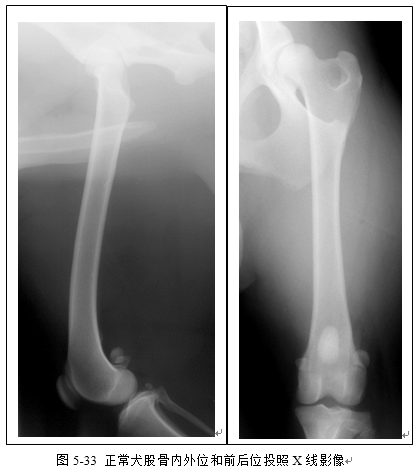

(3)识别胫腓骨、股骨、跗关节、膝关节X线影像(图5-32、5-33、5-34、5-35)。